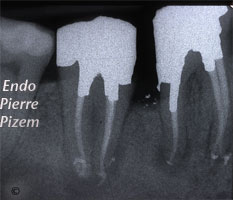

علاقة الانشطار و الوتد داخل قناة الجذر

دراسة Fuss et al 2001 أظهرت علاقة انشطار الجذور و وجود وتد داخل قناة الجذر كما يلي:

1) 62% من الجذور المنشطرة كانت تحتوي على اوتاد داعمة

2) 70% من مجموع الحالات اعلاه كان الوتد قصير ولم يصل الى ثلثي طول القناة

3) في اسوأ الظروف يفضل ان لايقل طول الوتد عن طول التاج

4) في دراسة Abou-Rass etal 1982 خلص الى ان طول الوتد في قنوات جذور الاضراس يجب ان لايتجاوز 7 ملم (القناة الوحشية Distal للطواحن السفلية / القنوات الحنكية Palatal للطواحن العليا)